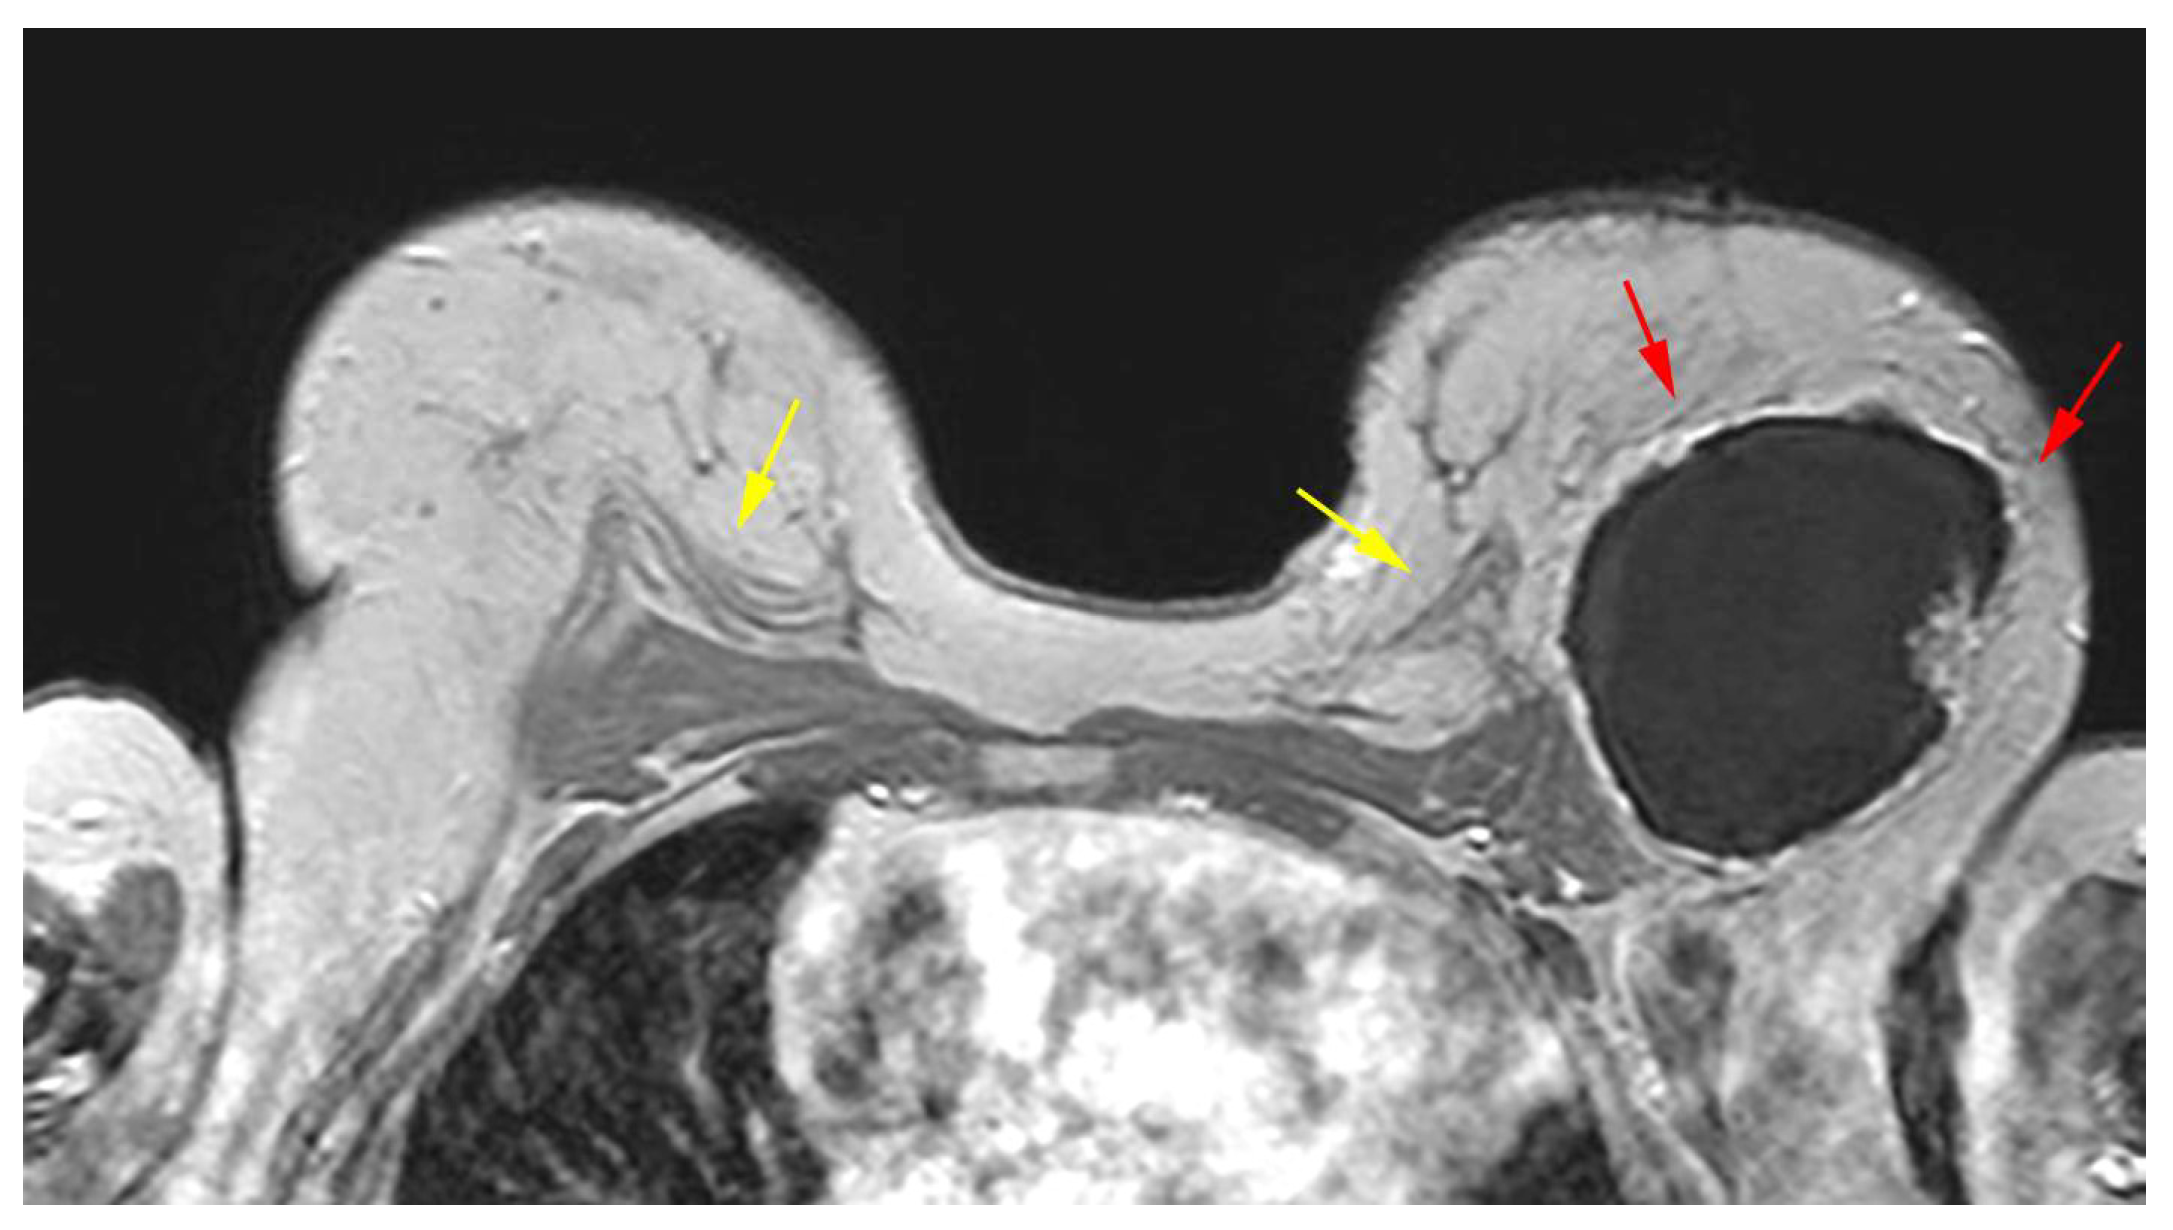

5.2.5. Implant Rupture

- Soo, M.S.; Kornguth, P.J.; Walsh, R.; Elenberger, C.D.; Georgiade, G.S. Complex radial folds versus subtle signs of intracapsular rupture of breast implants: MR findings with surgical correlation. AJR Am. J. Roentgenol. 1996, 166, 1421–1427. [Google Scholar] [CrossRef] [PubMed][Green Version]

- Safvi, A. Linguine sign. Radiology 2000, 216, 838–839. [Google Scholar] [CrossRef]

- Soo, M.S.; Kornguth, P.J.; Walsh, R.; Elenberger, C.; Georgiade, G.S.; DeLong, D.; Spritzer, C.E. Intracapsular implant rupture: MR findings of incomplete shell collapse. J. Magn. Reson. Imaging 1997, 7, 724–730. [Google Scholar] [CrossRef] [PubMed]

| Definitive rupture | Linguini sign | Low signal lines within the silicone |

| Subcapsular lines | Low signal lines parallel to the capsule surrounded by silicone | |

| Possible rupture | Keyhole or teardrop Sign | Focal silicone invagination between implant shell and fibrous capsule |

| Pitfalls | Complex radial folds | Long invaginations of the shell |